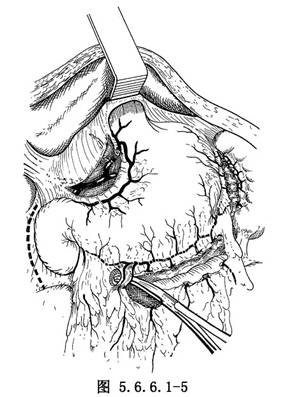

(3)游离胃:探查腹腔,如腹内无明显转移,在胃体上2/3与1/3交界处的小弯侧将胃肝韧带切开,再由相对应的胃大弯侧切开胃结肠韧带,用一条纱带越过胃后将胃向上牵引(图5.6.6.1-4)。继续切开胃结肠韧带,保留胃网膜右动脉,将韧带中的血管钳夹后切断结扎(图5.6.6.1-5)。切开胃脾韧带,切断结扎胃短动脉分支。在暴露术野时注意牵拉脾脏不能用力过大,以免撕裂脾脏(图5.6.6.1-6)。胃大弯侧游离足够以后,离断胃肝韧带,保留胃右动脉(图5.6.6.1-7)。在贲门下方附近的小弯侧摸到搏动的胃左动脉,用3把止血钳夹住,近侧两把,远侧1把,切断后先缝扎一道,再由其深部结扎一道(图5.6.6.1-8),缝扎胃侧血管断端。如此时胃左动脉近侧残端有出血,应先用指压住出血点,再请第一助手以拇指用力按压胸主动脉即可止血,用吸引器将积血迅速清除后,即可从容寻找到出血处予以处理。小弯侧游离完后,在离断贲门之前,请麻醉师将胃管连接在吸引器上持续吸引,将胃内容物尽量吸净,如此可以减少污染并方便吻合操作,吸引完后将胃管向外拔,使其尖端置于贲门上方3~4cm处。用大号直止血钳夹住贲门切断(图5.6.6.1-9)。胃侧断端用中号丝线贯穿缝合,再将浆肌层对拢间断缝合。食管侧断端用贯穿缝合封闭后用阴茎套保护之。将游离完毕的胃提至胸腔。